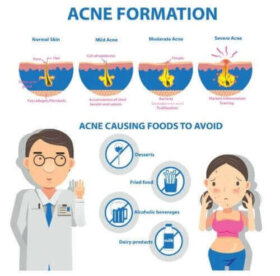

오늘은 응괴성 여드름의 주된 원인과 증상을 알아보자. 응괴성 여드름은 만성 형태의 여드름이다. 이는 흉터를 흉하게 하는 면포, 낭포성 결절, 누,…